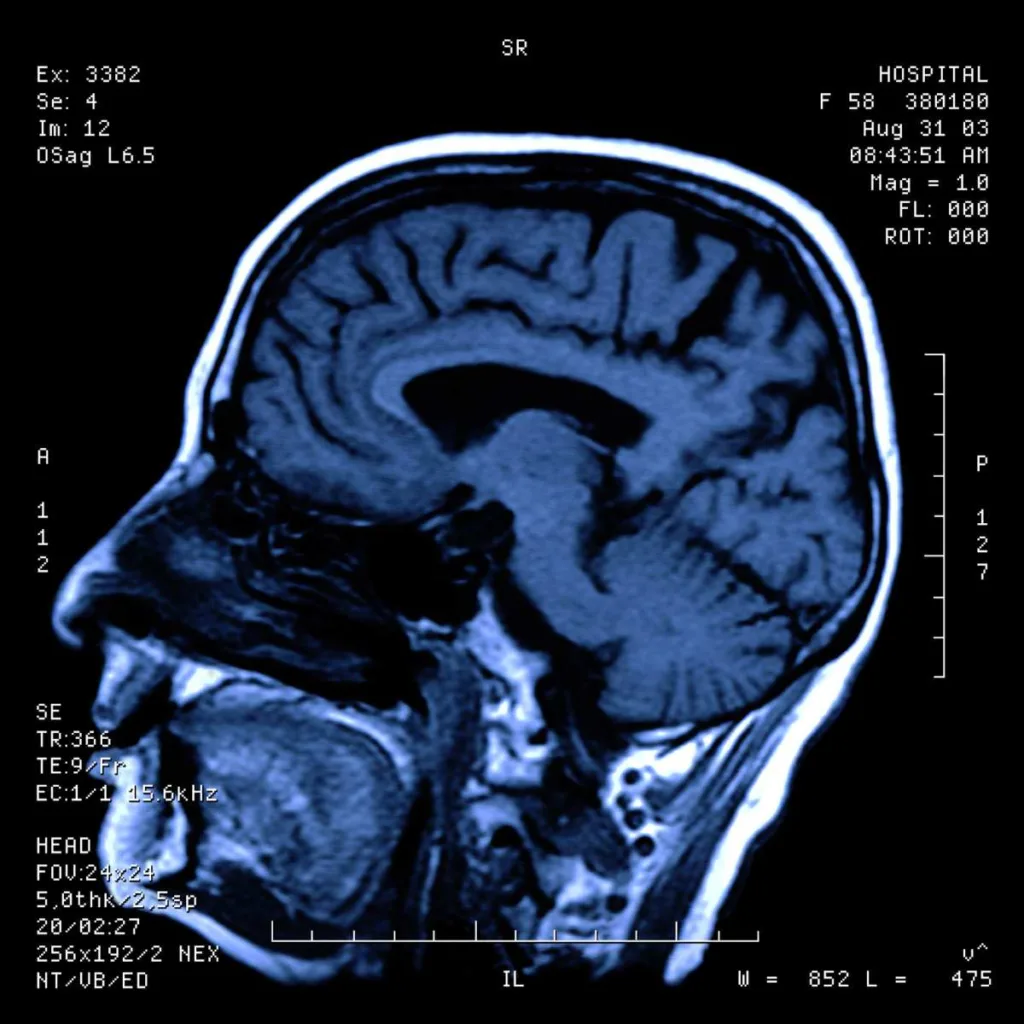

Resonancia Magnética de Cabeza